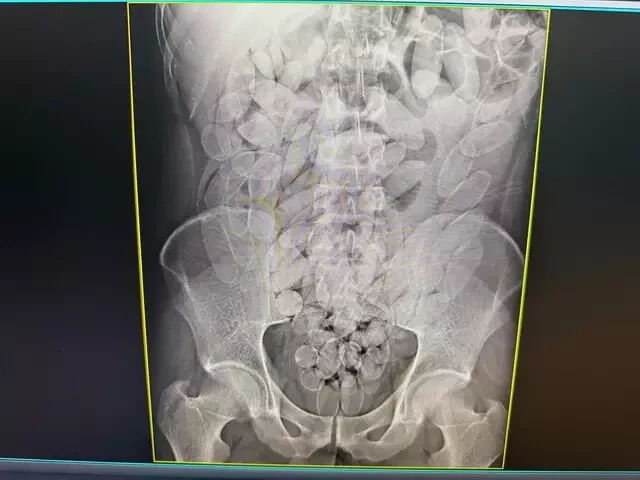

Os raios X confirmaram que os oito haviam engolido cápsulas de pasta base de cocaína. O material foi retirado de forma segura por equipe médica, totalizando 645 cápsulas. Após o procedimento, todos foram encaminhados à PF (Polícia Federal), onde permanecem à disposição da Justiça.